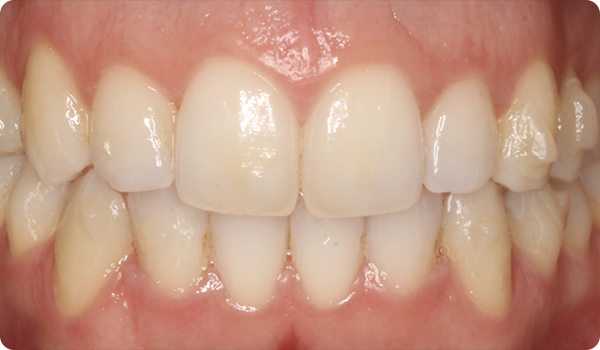

Efter en Right-behandling skal vi bevare patientens smil og forhindre, at tænderne vender tilbage til deres tidligere position.

Den endelige opfølgning på Right-behandlingen giver os mulighed for at fremstille retentionssystemet, Right Retainer.

Smil på plads

Med Right får dine patienter det smil, de ønsker, inden for den ønskede tid, på en komfortabel og "usynlig" måde.